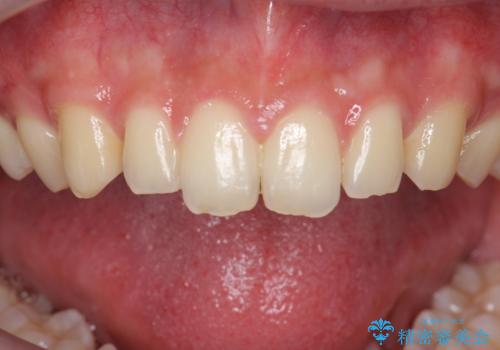

ナイトガードで歯ぎしり予防

- 歯ぎしりが気になるとの事で来院。

しっかりしたナイトガードが欲しいとの事だったので自費のナイトガードのご案内をしました。

ナイトガードは夜寝ている時、無意識に歯ぎしりをして歯がすり減ることを防ぐことがあります。また、歯が割れたり欠けたりするのも防いでくれます。